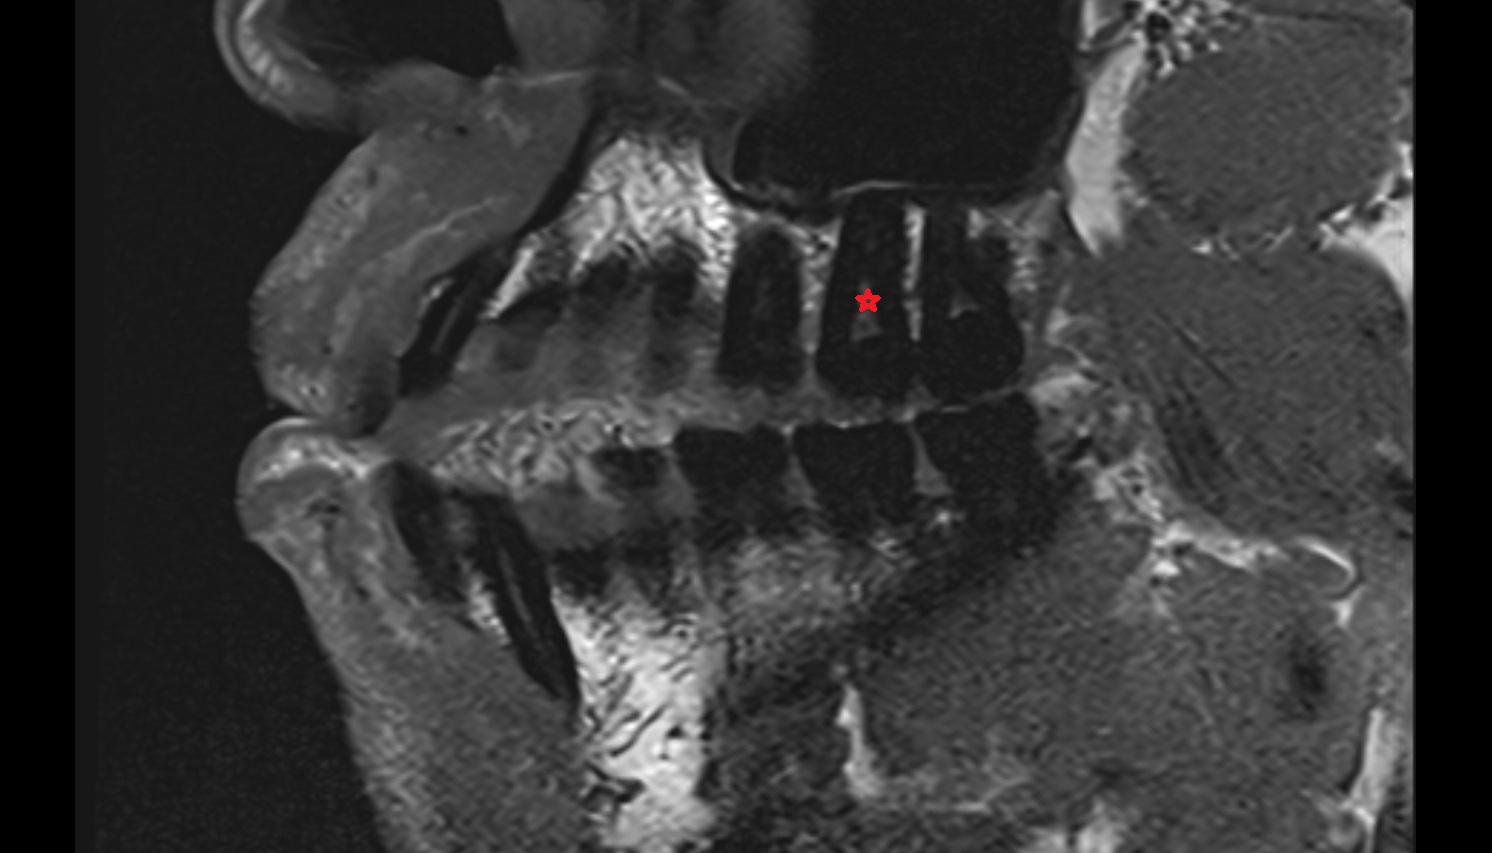

- Central inferior incisor tooth

- Central superior incisor tooth

- Lateral inferior incisor tooth

- Lateral superior incisor tooth

- superior canine tooth

- Superior first molar tooth

- Superior first premolar tooth

- Superior second molar tooth

- Superior second premolar tooth

- Superior third molar tooth

- Inferior canine tooth

- Inferior first premolar tooth

- Inferior second molar tooth

- Inferior second premolar tooth

- Inferior third molar tooth